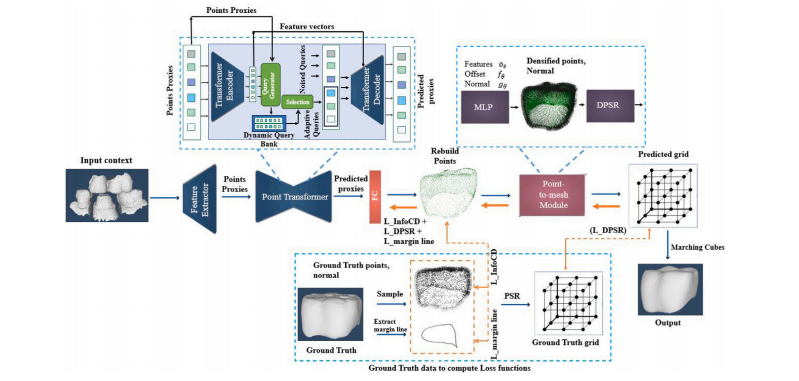

Our model is an end-to-end supervised framework that takes apartial point cloud context as input and generates the missing region ina mesh format. The overview of our framework is illustrated in Fig. 2. Itcomprises two key components: a transformer model for encoding anddecoding the data, and a specialized module designed to complete themesh. Distinctively, our framework applies contrastive learning to finetune the network, utilizing a Chamfer distance metric. Furthermore, theframework is enhanced by a custom function specifically designed tometiculously refine the margin line of the crown. Moreover, we utilize amean square error function to achieve precise control over the crown’sindicator grid. The following sections provide a detailed analysis ofeach component within our network, along with the loss functions wehave implemented.

我们的模型是一个端到端的监督框架,它将部分点云信息作为输入,并以网格格式生成缺失的区域。我们框架的概览如图2所示。它包含两个关键组件:一个用于对数据进行编码和解码的Transformer模型,以及一个专门设计用于完成网格的模块。独特的是,我们的框架应用对比学习,利用倒角距离度量来对网络进行微调。此外,该框架还通过一个专门精心设计的自定义函数得到增强,该函数用于精细优化牙冠的边缘线。而且,我们使用均方误差函数来实现对牙冠指标网格的精确控制。接下来的部分将对我们网络中的每个组件,以及我们所采用的损失函数进行详细分析。

Fig. 2. Architecture flow of our proposed model, highlighting key components such as DPSR (Differentiable Poisson Surface Reconstruction), FC (Fully Connected Layer), and MLP(Multi-Layer Perceptron)

图2:我们所提出模型的架构流程图,突出显示了关键组件,例如可微泊松曲面重建(DPSR)、全连接层(FC)以及多层感知器(MLP)。